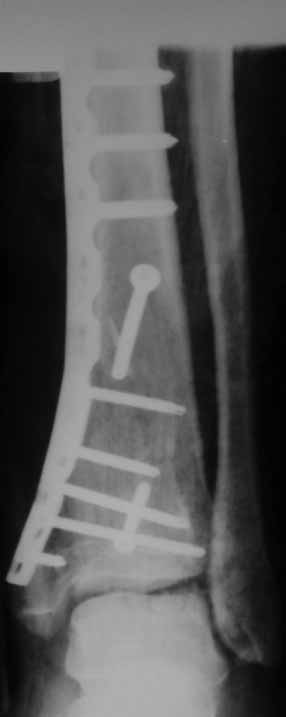

Отчет по "пилону":)))

Извиняюсь пропал - оперировал "пилон". В форуме не хотел обсуждать финансовые возможности пациента. Потянул комбинированную пластину. Опыт общение с пластиной "крест" есть - не очень понравилось - слишком много места занимает, даже с учетом обрезаний лишнего. Сделал доступ огибающий медиальную лодыжку спереди. В переднем крае оказался достаточно крупный отломок - удалось зафиксировать винтом. Дефекта кости не оказалось.

Какой таран? в одном сегменте повреждается одно или другое. Крайне редко обе части. Анатомическая репозиция безукоризненна,но для чего межфрагментарный винт при использовании LCP это очевидное нарушение методики. А по поводу Мальтийского креста, то это оличный незаменимый, в ряде случаев, фиксатор, но не для этого перелома, абсолютно!С Уваением! Сергей.